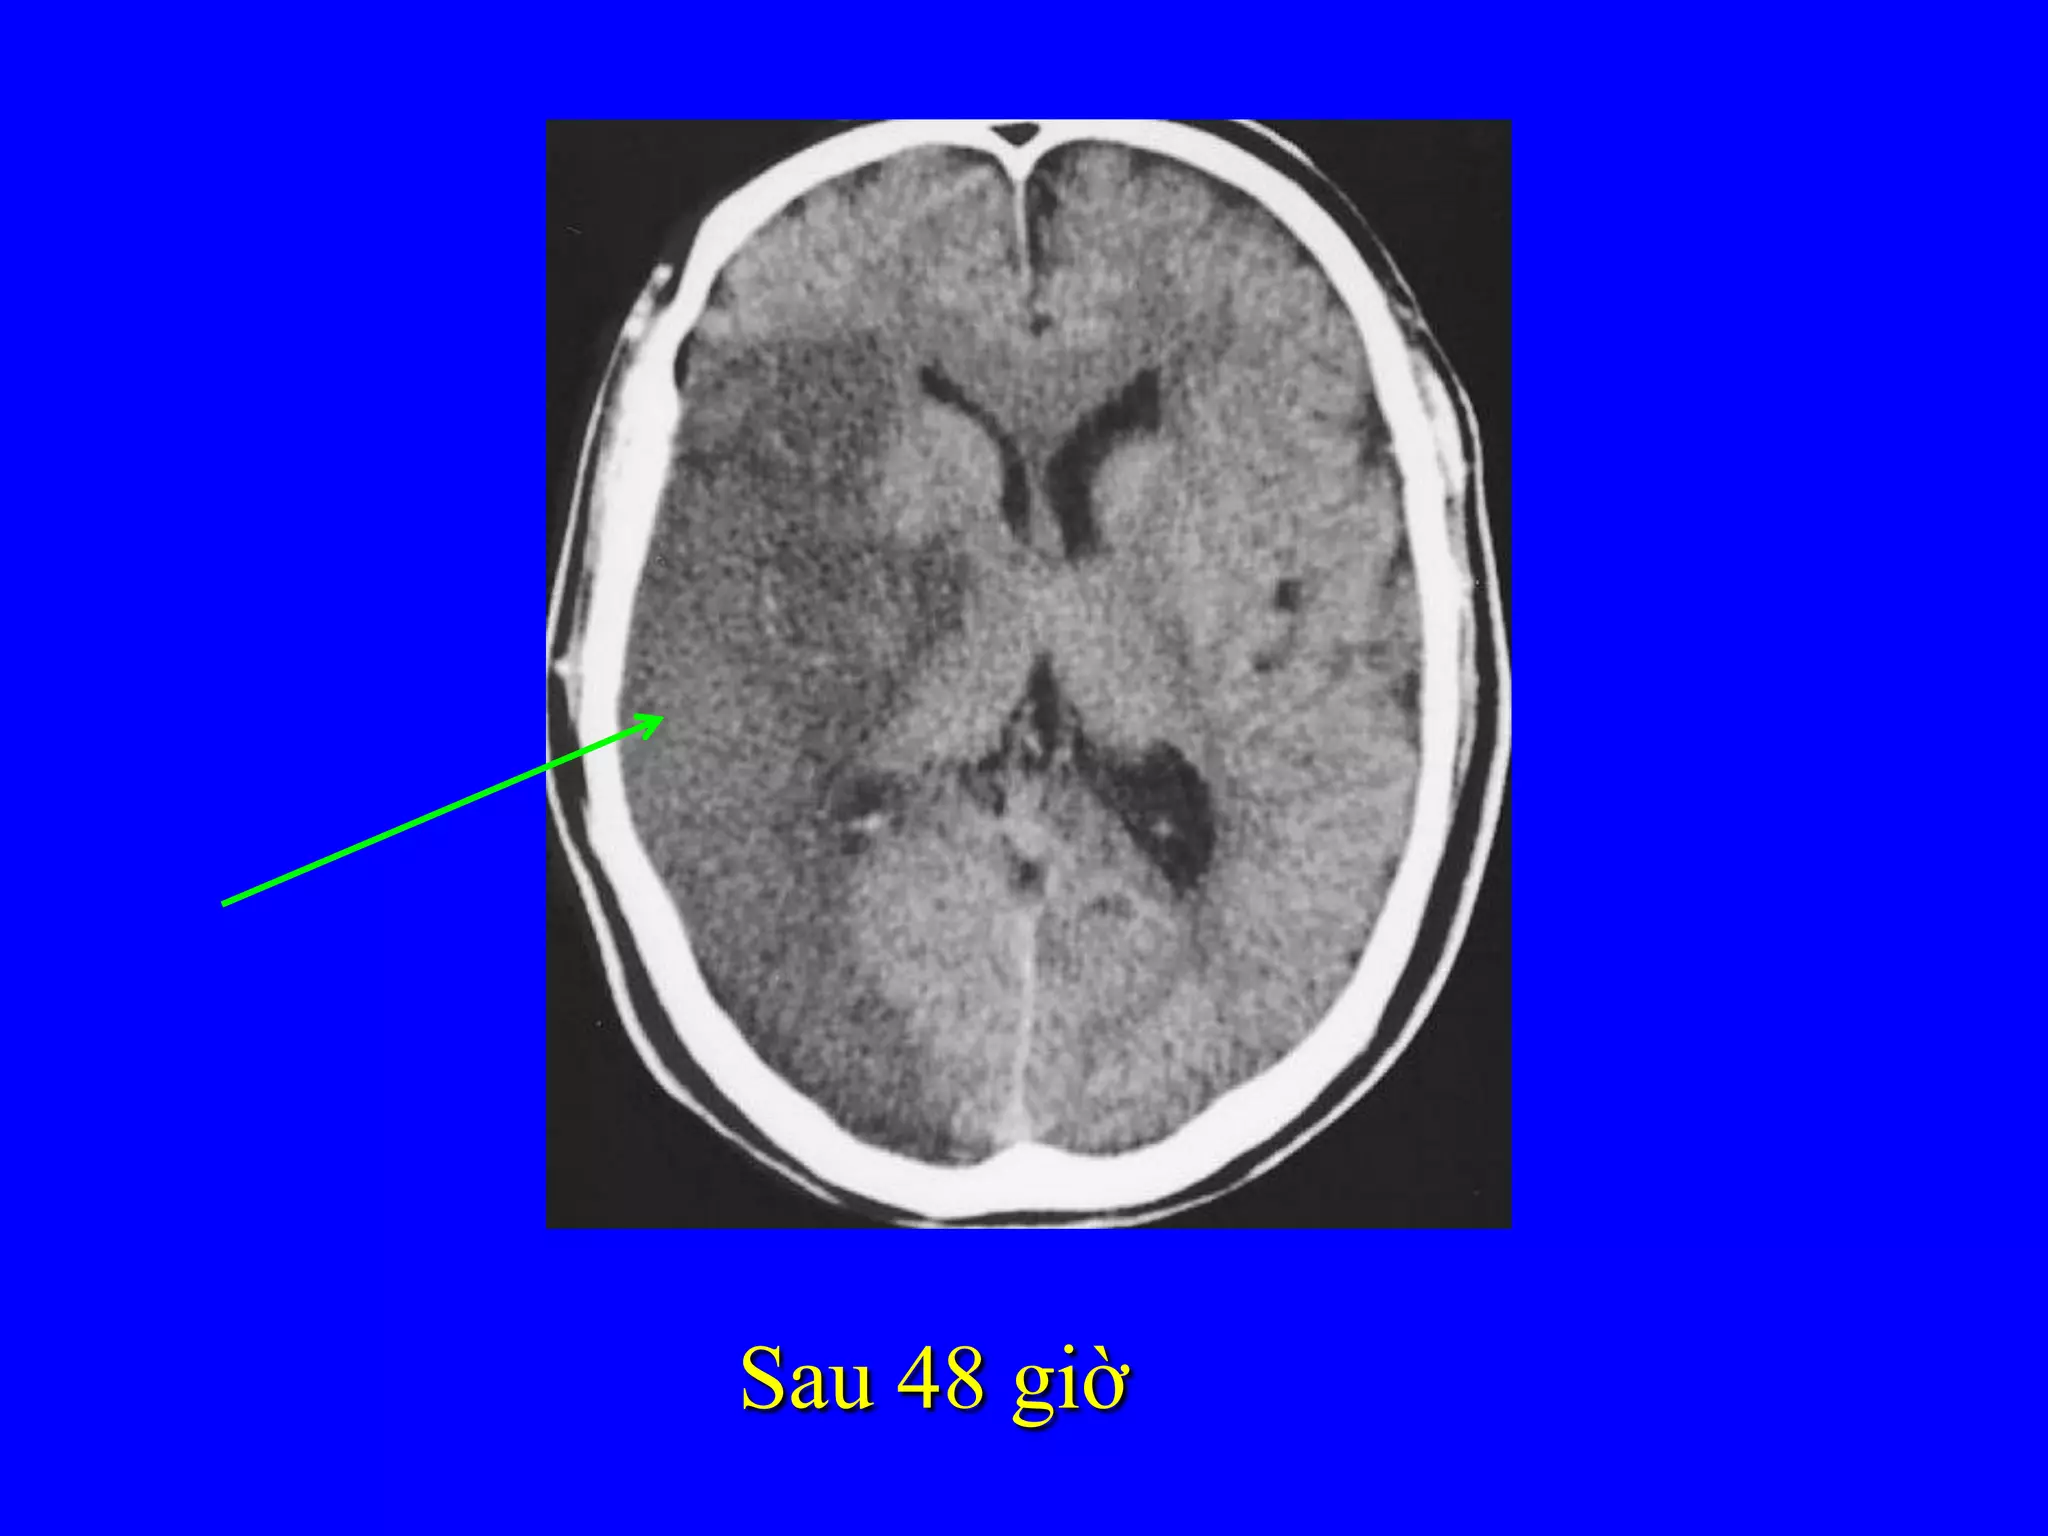

Hình tăng tín hiệu động mạch não giữa

Ngay khi vào viện

Sau 48 giờ

Chẩn đoán hìnhảnh • Chụp cắt lớp vi tính sọ não (không tiêm thuốc cản quang)  Phân biệt chảy máu não trong những giờ đầu  Một số hình ảnh gián tiếp nhồi máu não Warlow C et al. Stroke. Lancet 2003

Hình tăng tínhiệu động mạch não giữa